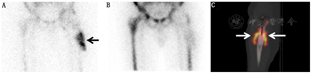

此外,SPECT/CT显像在诊断人工关节感染方面的价值同样令人期待[57,58,59,60,61,62]。Tam等[57]报道称SPECT/CT骨显像的CT显像可发现SPECT图像中放射性浓聚区相应部位的形态学异常。关节肿胀、关节囊积液和肌肉水肿是诊断感染灵敏且特异的表现,这些均可通过CT显像发现。Al-Nabhani等[58]报道称,SPECT/CT骨显像可为80%以上膝关节置换术后疼痛的患者提供有用信息。Filippi和Schillaci[59]报道称99Tcm标记白细胞SPECT显像诊断的准确性为64%,而SPECT/CT显像可提高到100%。SPECT/CT可精确定位浓聚的标记白细胞,利于软组织感染与骨骼感染的鉴别。Kim等[60]报道,标记白细胞平面显像的灵敏度、特异性和准确性分别为82.0%、88.0%和84.8%。而SPECT/CT显像的灵敏度、特异性和准确性可提高至93.3%。SPECT/CT显像可精确定位感染病灶,并准确划定感染范围(图6)。